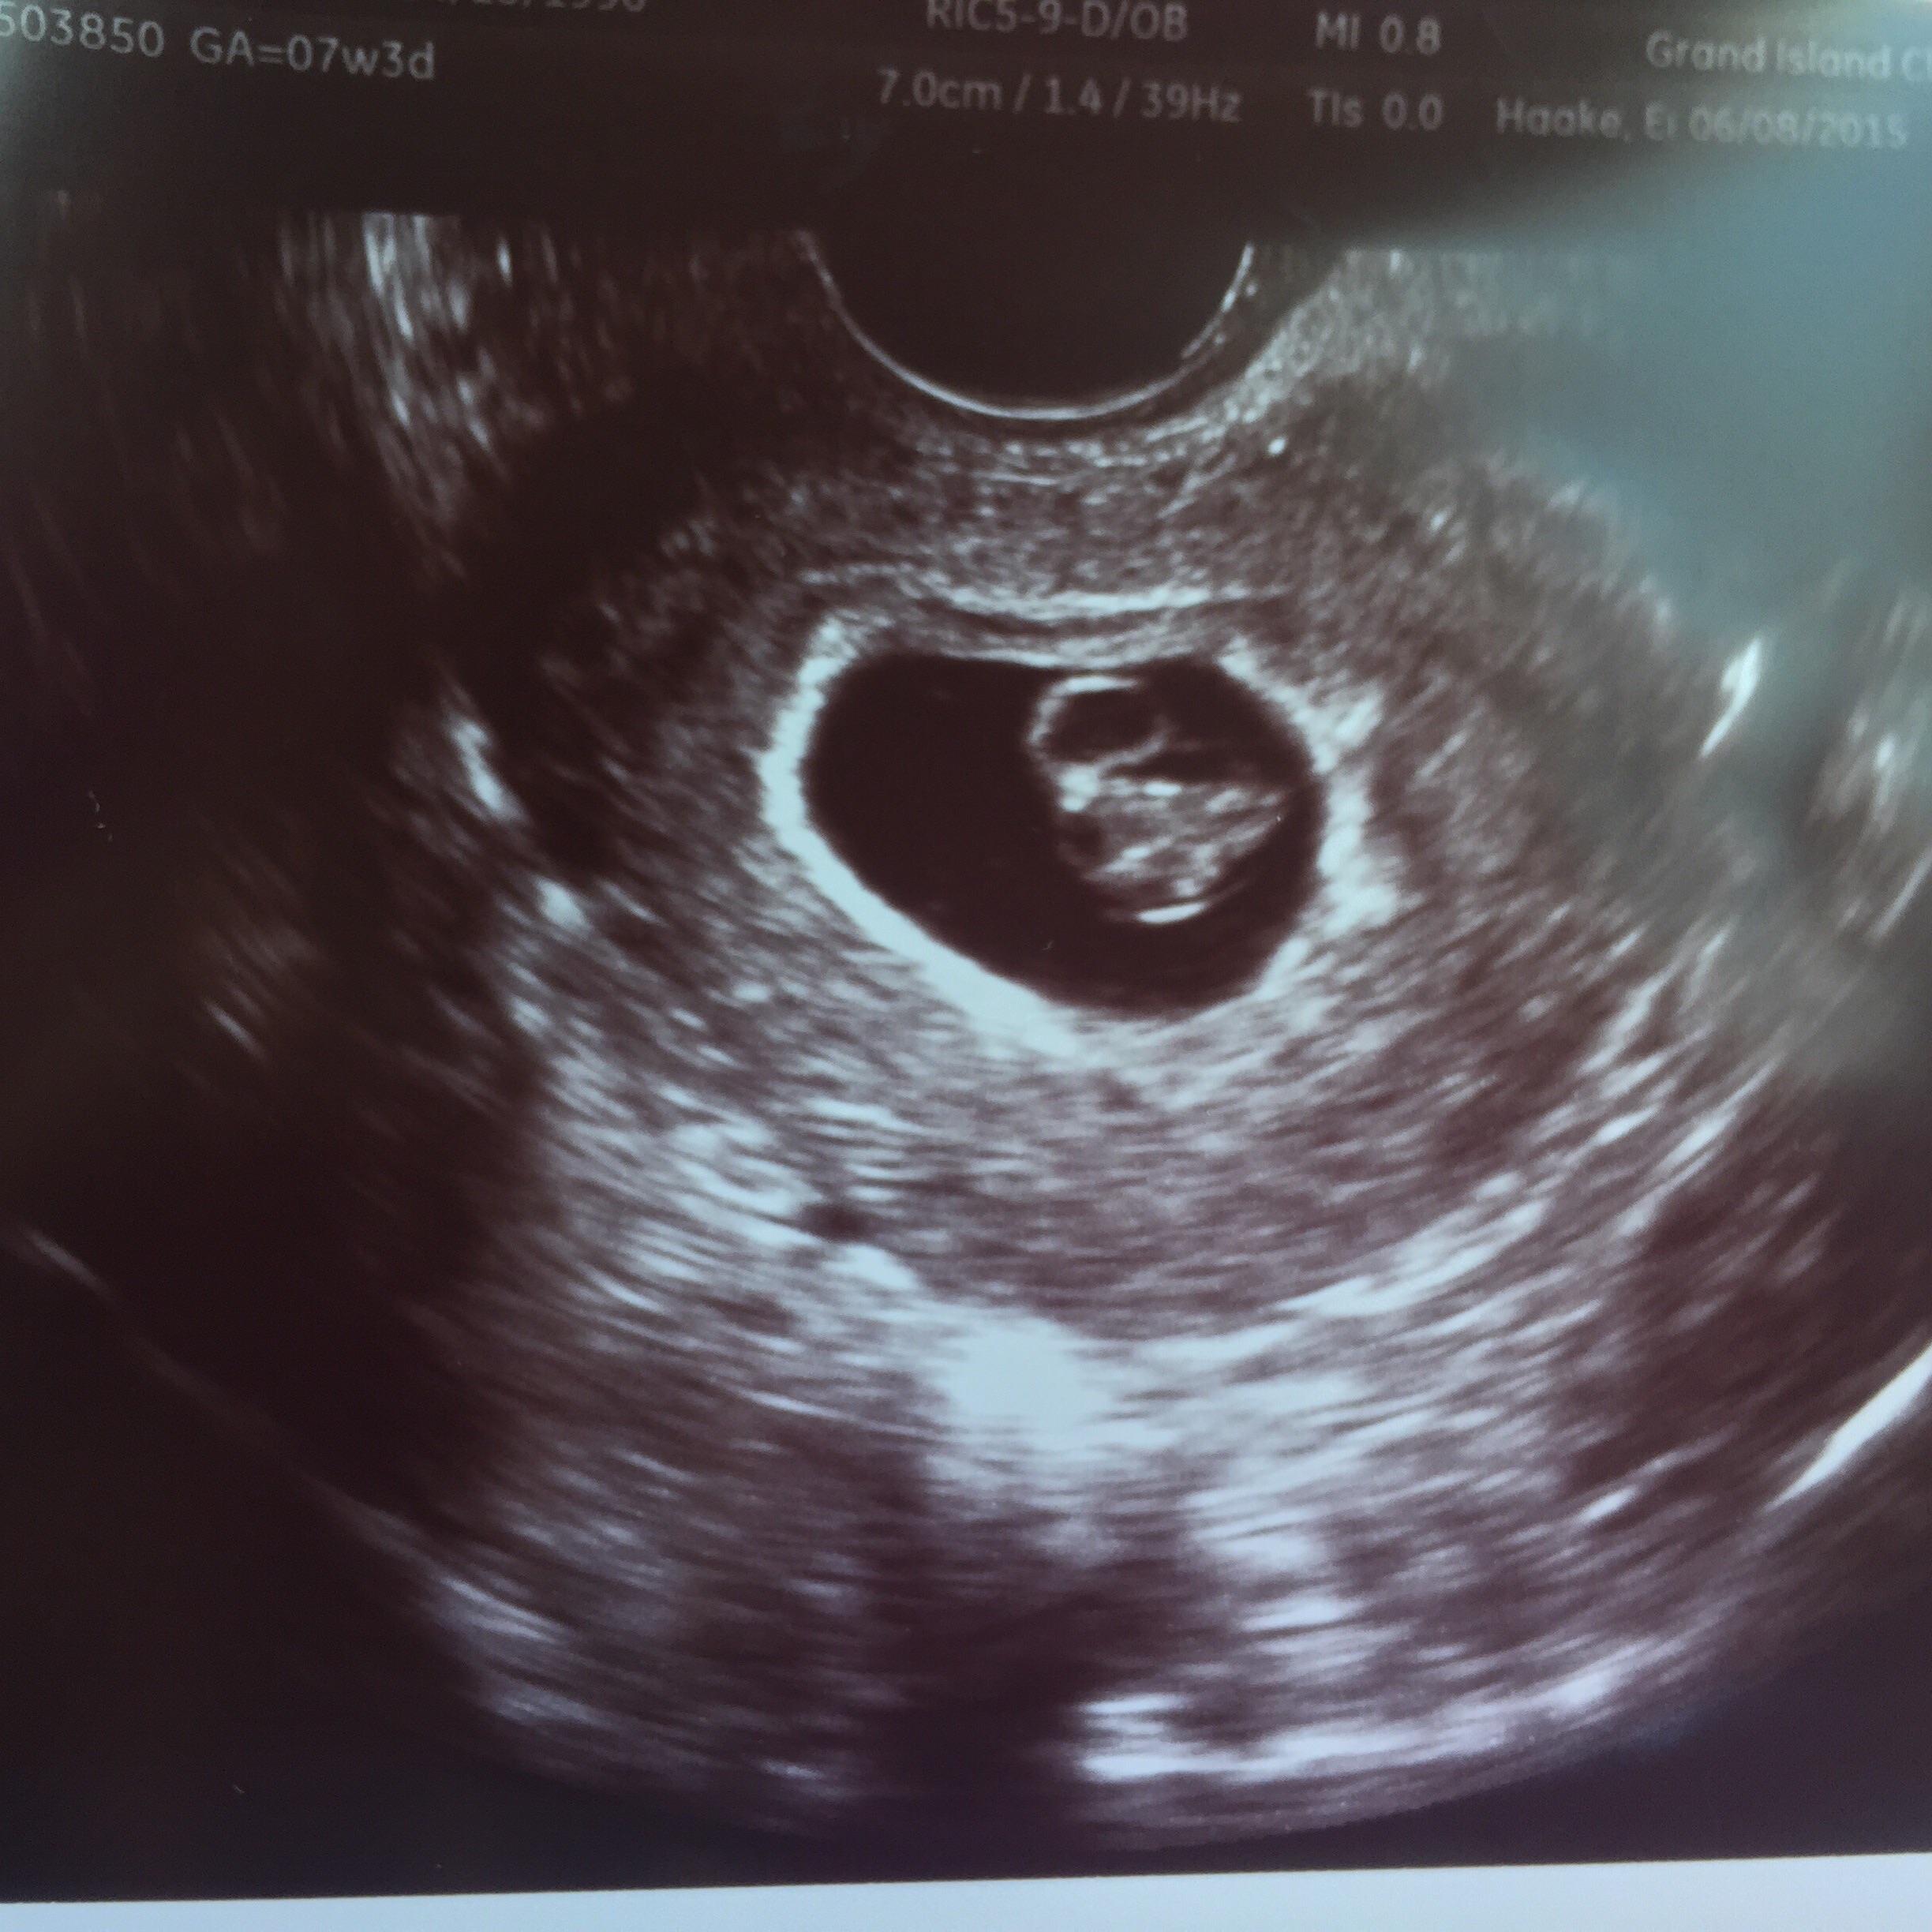

Found out last night that some girl I have on Facebook stole my ultrasound, claimed a miscarriage and is pretending my baby is here now "dead baby"... so sickening.

My ultrasound has my name on it, however when I uploaded it, it only had the date of the ultrasound, my doctor and how far along I was. I will upload both pictures for comparison.

She's called out on my Facebook, it was the first thing I did so people could see how sick she was. She claimed to be 16 weeks, miscarried and that it was an ectopic pregnancy.